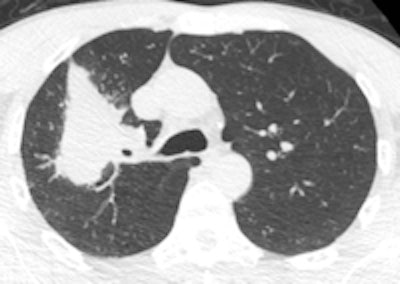

A 50-year old male patient with NSCLC stage pT2b pN2 cM0, imaged with FDG-PET/CT-MR. On coronal PET maximum intensity projection (MIP) image, an FDG-avid tumor in the right upper lobe and a mediastinal lymph node metastasis are seen. All images courtesy of Dr. Martin Huellner.For many years, PET/CT has been the standard modality for staging NSCLC patients. So, before PET/MRI can supplant it for this application, some basic clinical questions need to be addressed, said lead author Dr. Martin Huellner from University Hospital Zurich.